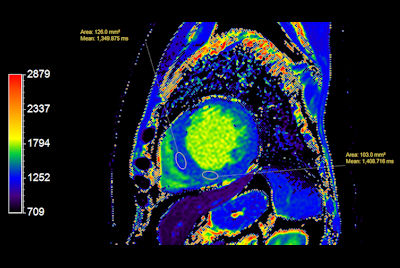

Myocardial infarction with T1/T2 Mapping